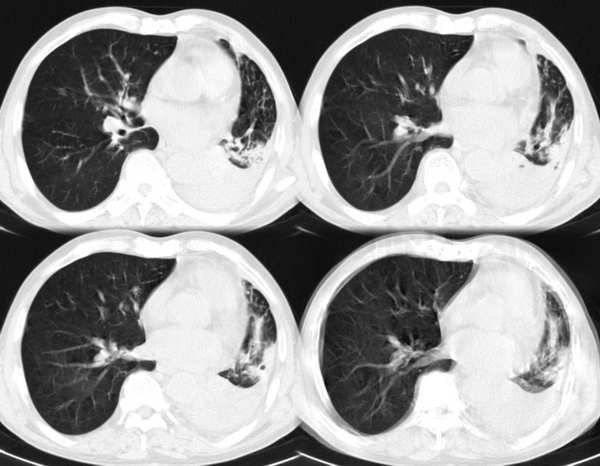

m67y外院ct诊断肺ca,现来我科复查ct

左肺下叶支气管狭窄局部见肿块影左肺下叶不张,肺癌应该没问题吧

典型中央型肺ca

左主支气管变窄,左下叶部分不张,考虑肺癌可能性大

考虑左下肺中央型肺癌并肺不张,建议支气管镜检查。

左下肺中央型肺癌并不张可能性大,为慎重起见,请楼主提供病史,以排除支气管内膜结核引起肺不张。

主-肺动脉窗似有大的淋巴结,肝也像有多发低密度灶。看不太清,是不是转移?

左中央型肺癌并左下叶肺不张,建议纤支镜检查.

左下肺中央肺ca并下肺不张